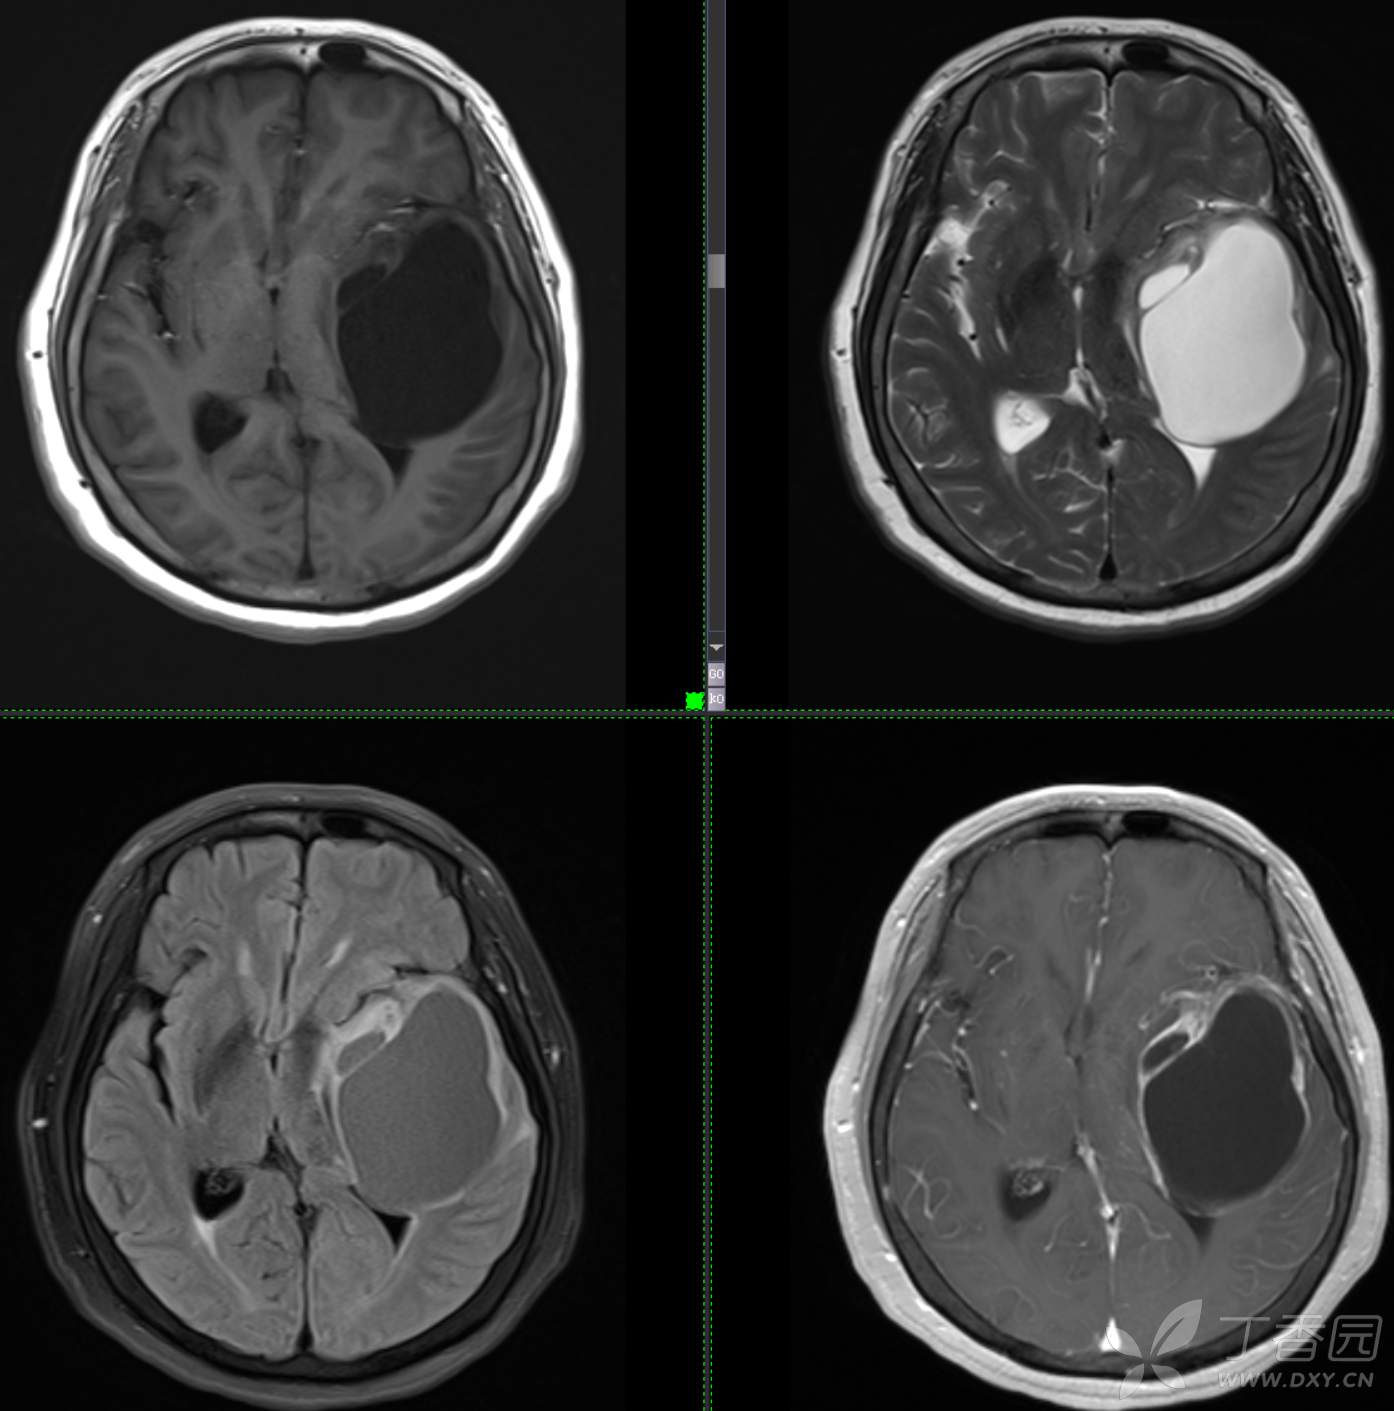

头颈组12:老年女性,原发?继发?

患者年龄:58岁

现病史: 【患者1月余前无明显诱因出现记忆力减退,易忘记事情,表现为忘记说过的话、易忘 事、理解力及计算力均尚可、阅读无受限、无性格脾气改变,无头痛头晕、无恶心呕吐、无视物模糊,无言语不利,无幻觉妄想,当时未重视未就诊。1月内记忆力减退进行性加重,对刚做过的事情即遗忘,计算力下降,日常生活尚能自理。遂至我院门诊就诊,查“颅脑CT平扫:左侧基底节-颞叶区低密度占位,建议进一步增强 MRI检查。

患者既往子宫内膜癌手术史;高血压病史3年